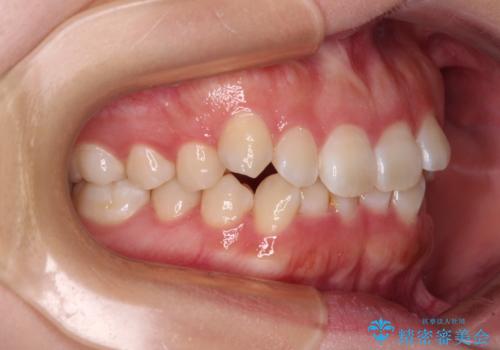

前歯のデコボコを整える インビザラインによる矯正治療

- 上下前歯のデコボコを気にして来院された患者様です。

叢生は軽度であり、ワイヤー矯正でもマウスピース矯正でも対応可能であったので、好きな装置を選んでもらいました。

相談の結果、インビザラインによる矯正治療を行うこととしました。